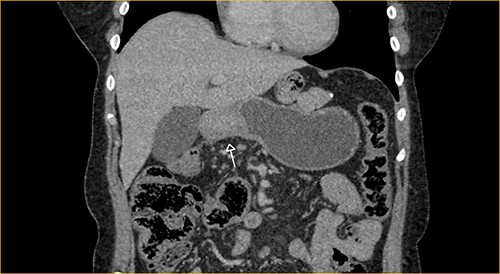

Laboratory examination showed anemia. An excluded stomach distention and parietal thickening of the pylorus and antrum were identified during abdominal computed tomography (CT) and magnetic resonance imaging (Figs 1–4). Thoracic CT was normal.

Transversal section on T2-weighted magnetic resonance showing excluded stomach distention with parietal thickening of the pylorus and antrum (arrow).